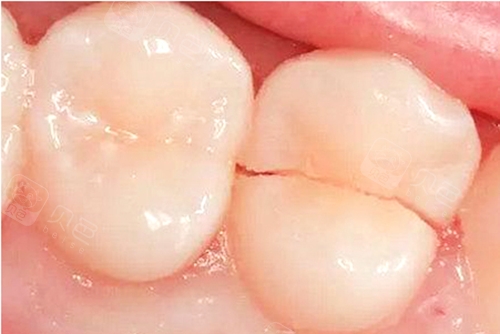

牙隐裂、牙齿非龋性破坏疾病

牙齿牙尖过尖、咬合过紧、牙齿发育不良等可导致牙齿出现裂纹,另外有的人习惯长期咀嚼硬物,甚至牙齿开啤酒盖等习惯,也可导致牙齿隐裂或缺损,严重的牙齿隐裂或缺损可致牙齿劈开且无法保留,导致缺牙。牙齿磨耗和楔状缺损也是导致老年人牙体和牙列缺损的主要原因。

隐裂的牙齿从中间劈裂开导致患牙无法保留